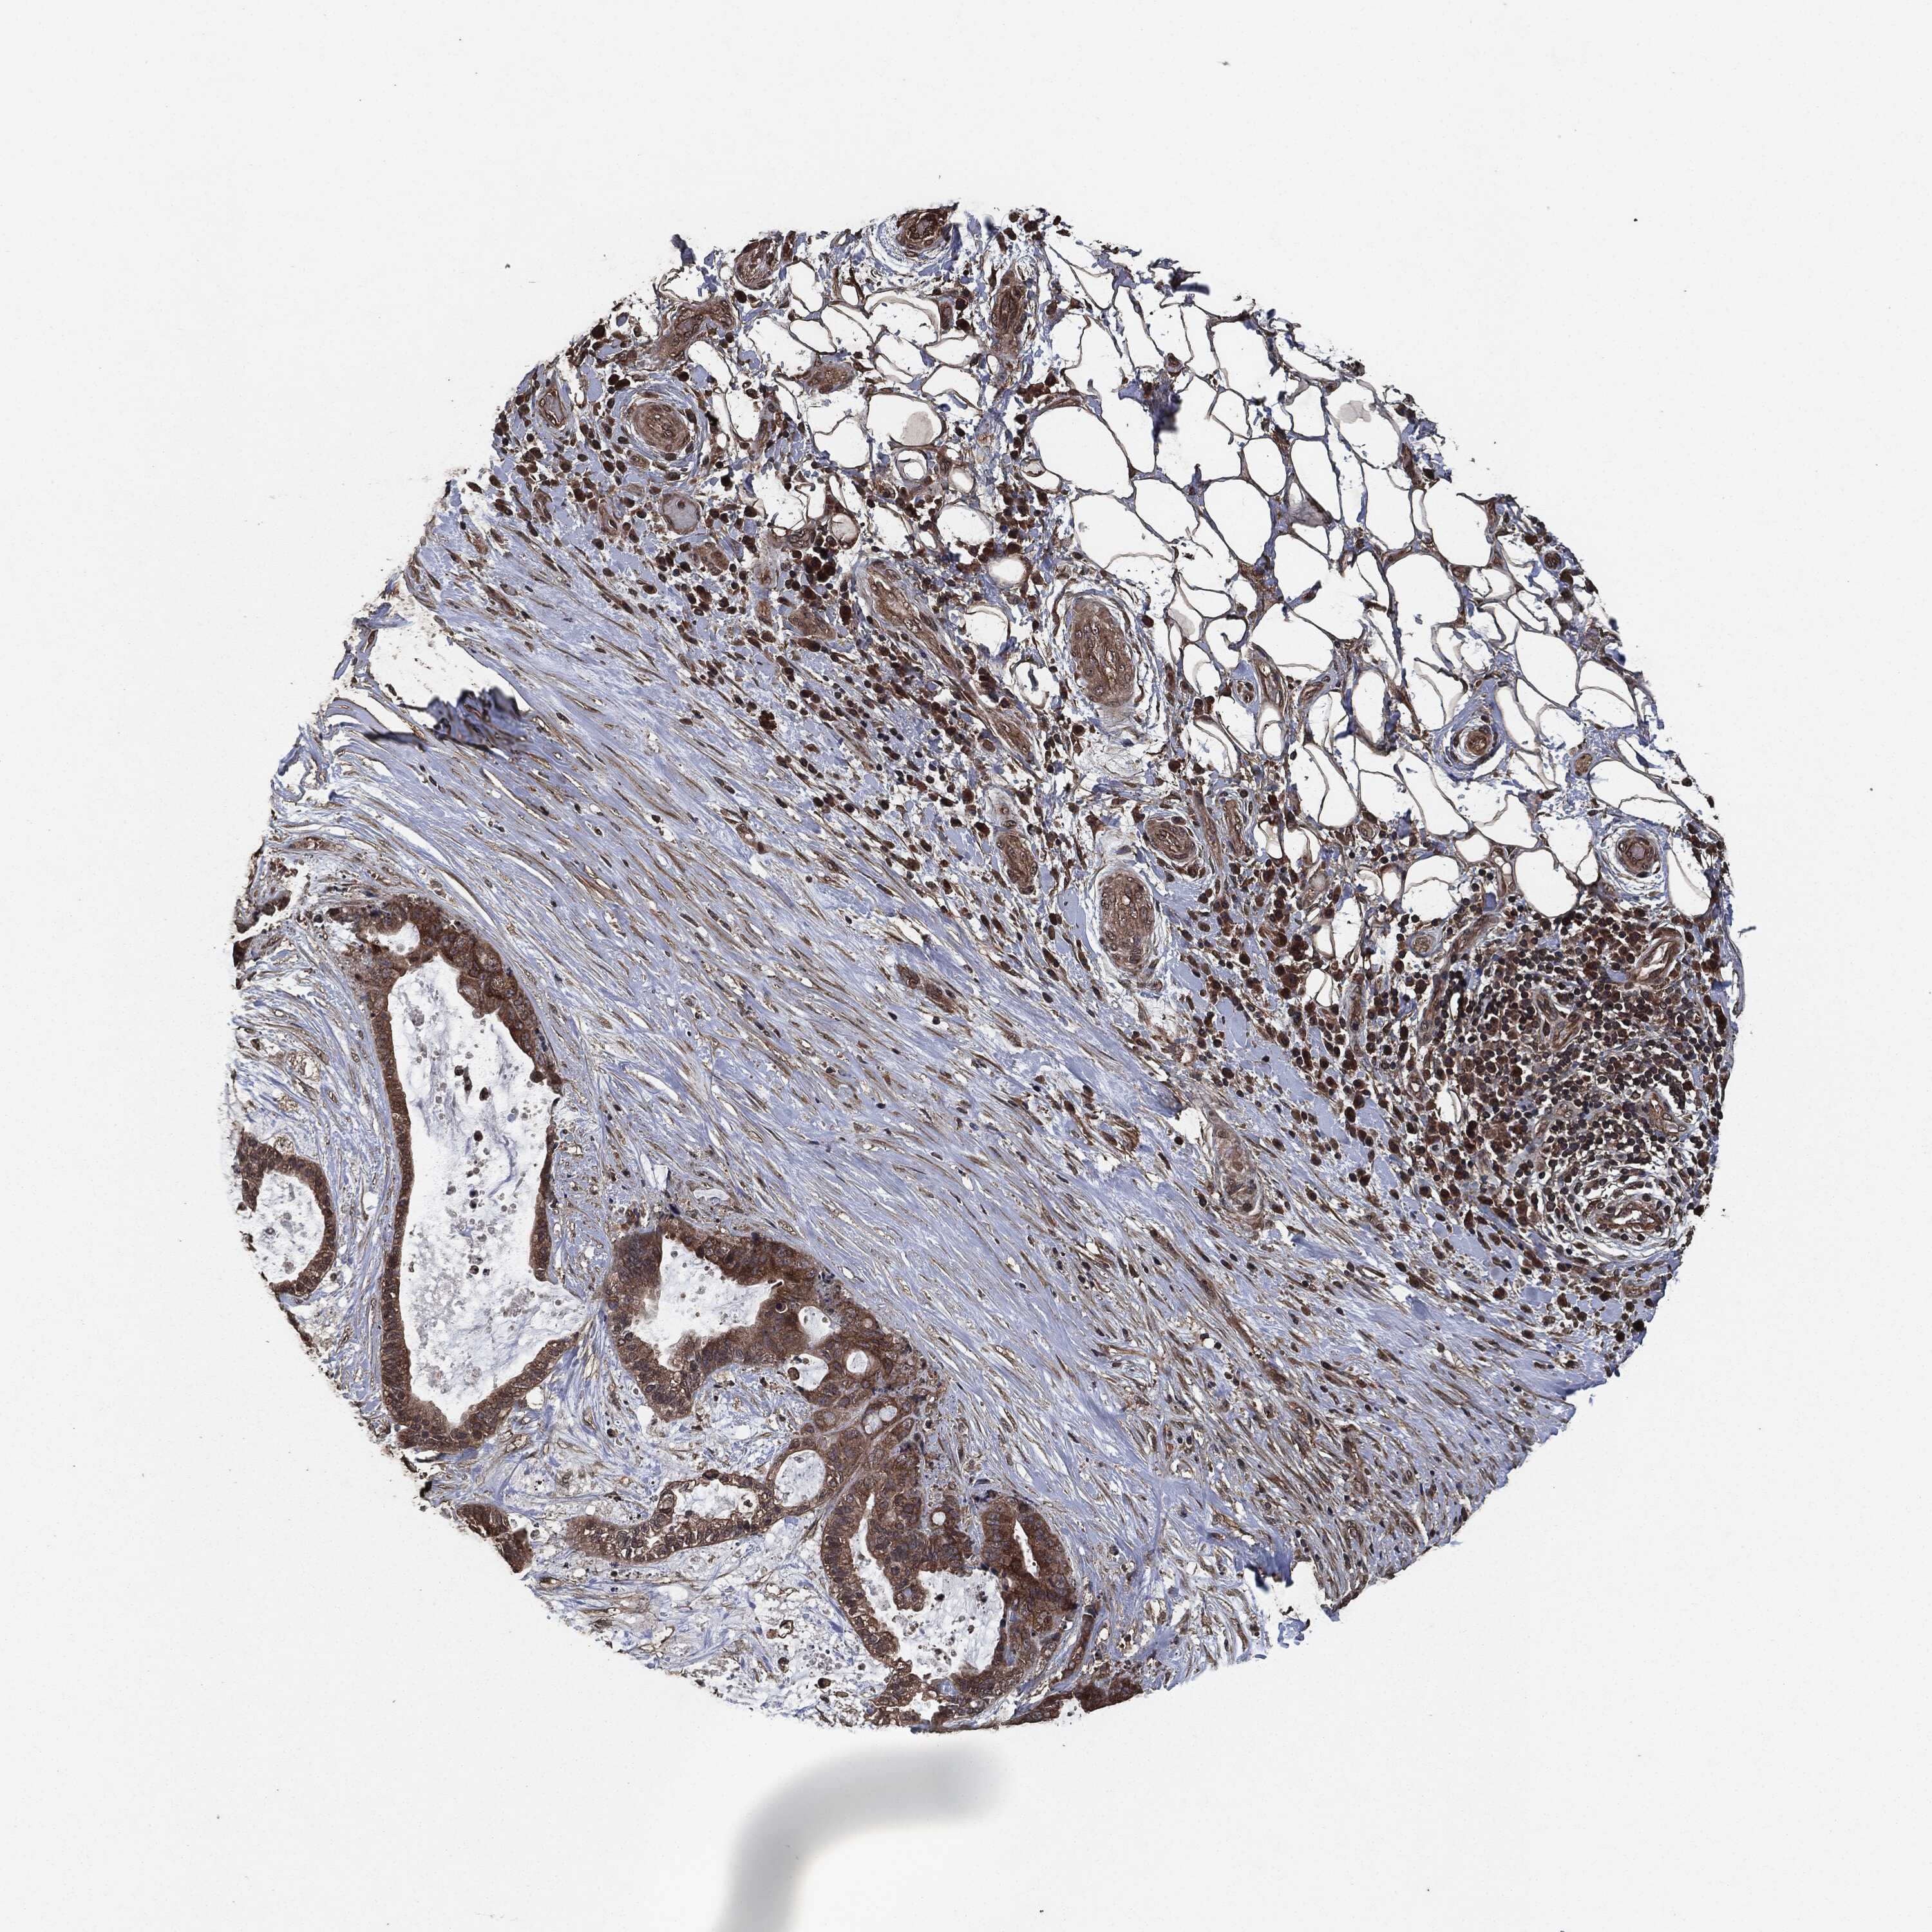

LIVER CANCER - Protein expressioni

A mouse-over function shows sample information and annotation data. Click on an image to view it in a full screen mode. Samples can be filtered based on level of antibody staining by selecting one or several of the following categories: high, medium, low and not detected. The assay and annotation is described here.

Note that samples used for immunohistochemistry by the Human Protein Atlas do not correspond to samples in the TCGA dataset.

Antibody stainingi

Antibody staining in the annotated cell types in the current human tissue is reported as not detected, low, medium, or high, based on conventional immunohistochemistry profiling in selected tissues. This score is based on the combination of the staining intensity and fraction of stained cells.

Each image is clickable and will lead to virtual microscopy that enables deeper exploration of all samples and also displays staining intensity scores, fraction scores and subcellular localization as well as patient and tissue information for each sample.

Antibody HPA064427

Antibody HPA075510

Antibody CAB021903

Staining

High

Medium

Low

Not detected

Intensity

Strong

Moderate

Weak

Negative

Quantity

>75%

75%-25%

<25%

None

Location

Nuclear

Cytoplasmic/membranous

Cytoplasmic/membranous,nuclear

Carcinoma, Hepatocellular, NOS

Cholangiocarcinoma